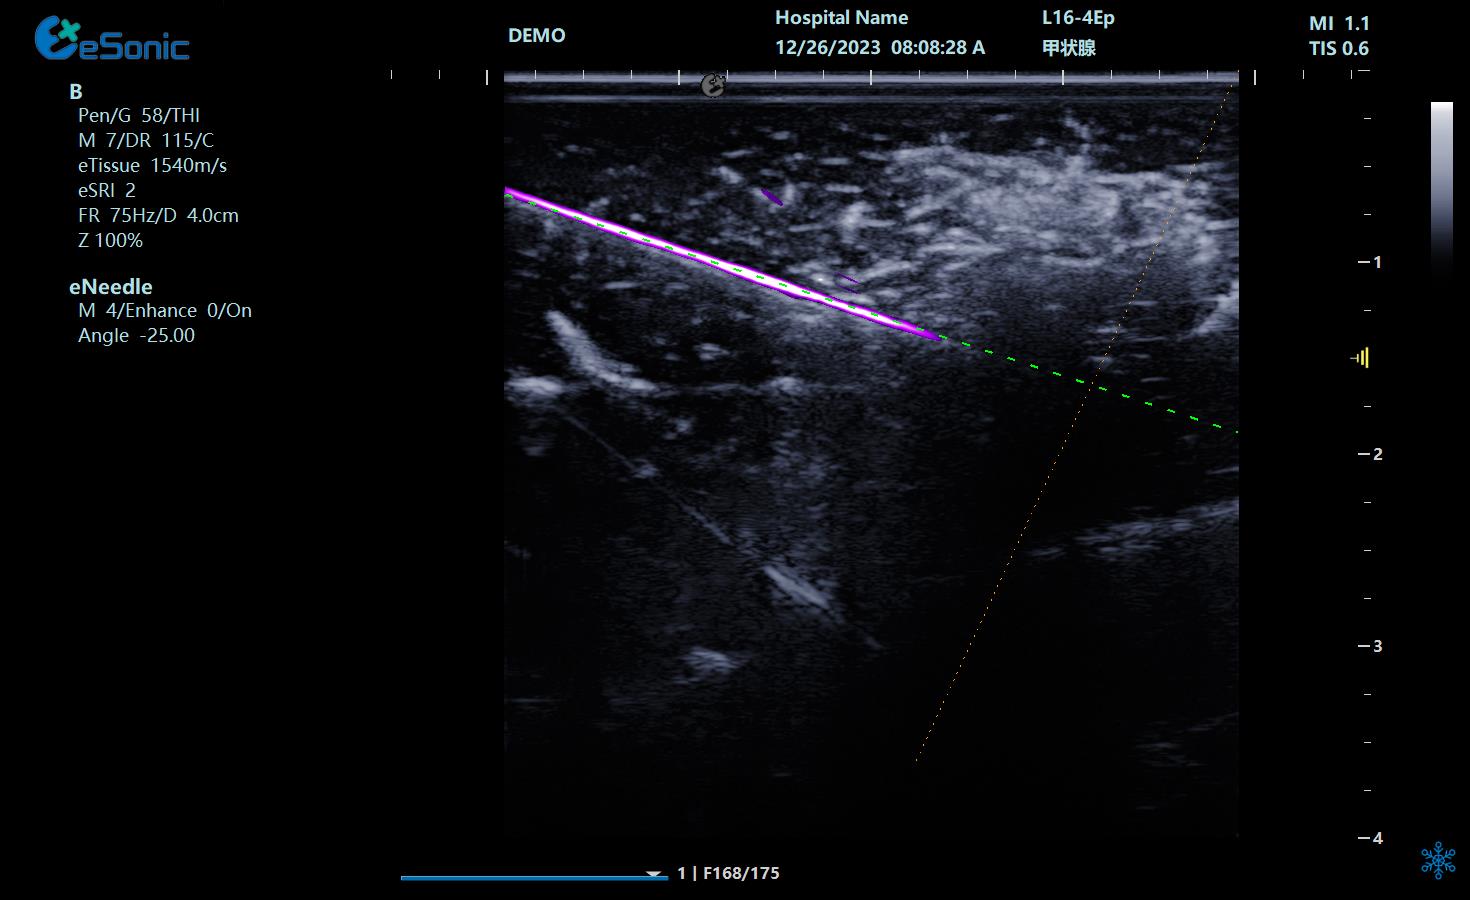

NeedleTS?穿刺针智能解决方案

?穿刺针增强显影?智能MAP?无磁导航

为临床医生有创穿刺保驾护航,真正实现精准导航。

5c8590e498a3b927e1f709e192d7ee7.png